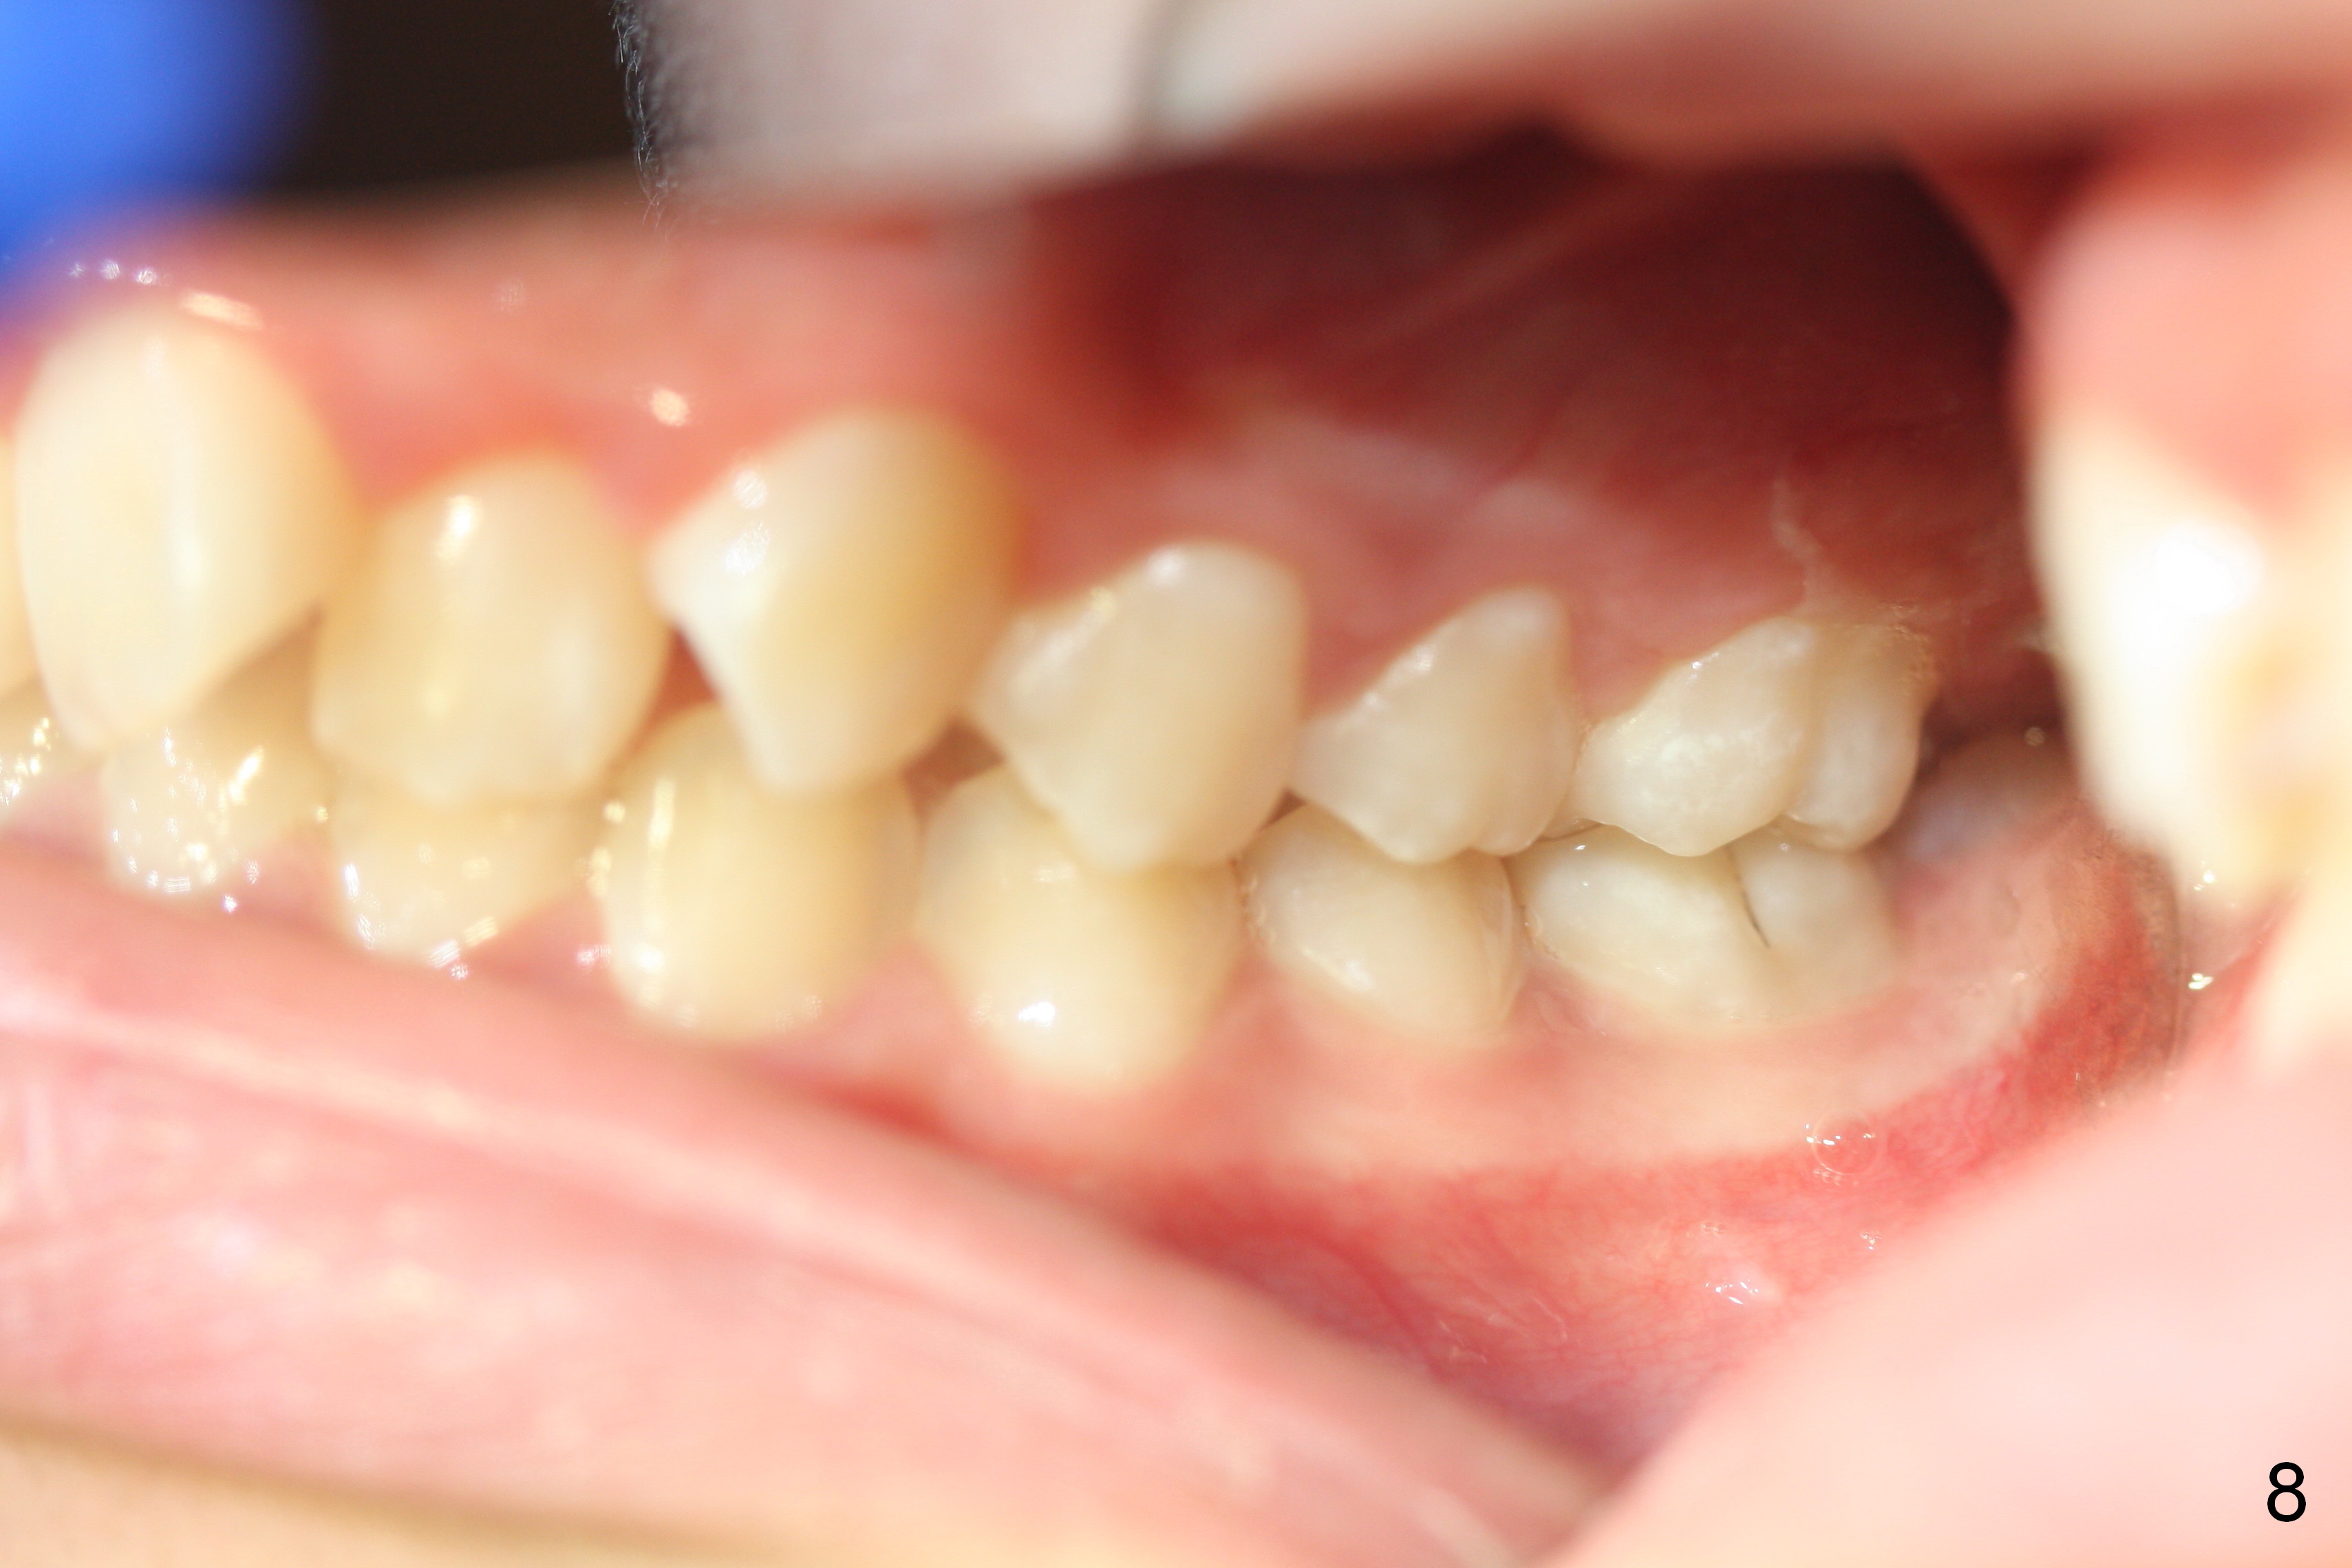

A 13-year-old girl presents for orthodontic consultation.  Chief complaint is crooked teeth.  Her brother is finishing 4 extraction ortho.

Looking at the records, the lower incisors are protrusive and have crowding, so think extraction.  There is enough combined crowding and class II to warrant extraction.  Since there is lower crowding, it would be 4 bicuspid extractions with the sliding mechanics using elastics or Niti closing coil springs. Closing the extraction space by maintaining the lower incisor position and moving the lower molars forward.  The upper arch is 50/50 front going back/back coming forward. Dr. Doug Ness, March 13, 2015 1:18 AM